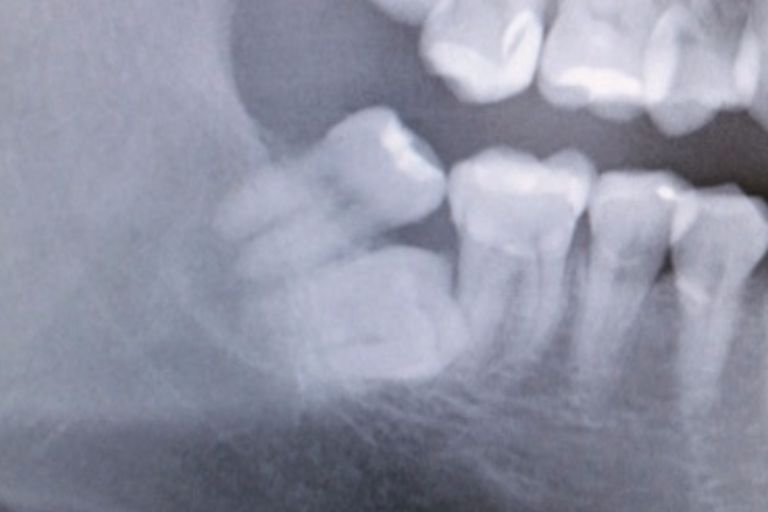

☆☆☆

神経と親知らずが非常に近く,抜歯をすると麻痺が出る可能性が非常に高そうです.二回に分けて親知らずを抜くことにしました.

まず,歯の頭の部分を分割します.神経に非常に近いので分割も細心の注意を払って行います.

歯の頭だけを除去しました.そのスペースに根っこが移動してくるのを半年ほど待ちます.これももちろん保険適応です.自費のところもあるみたいです.